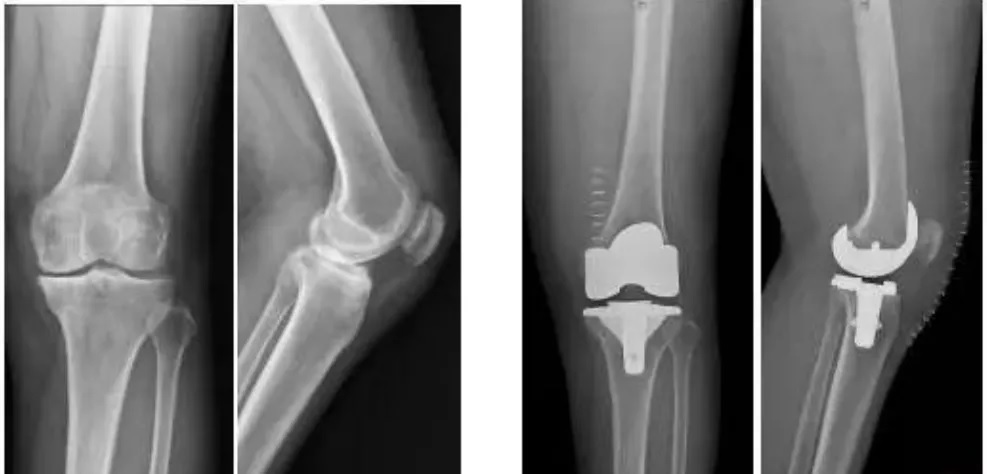

9月30日,四川大學(xué)華西醫(yī)院骨科的周宗科教授團(tuán)隊(duì)成功為患有膝關(guān)節(jié)骨關(guān)節(jié)炎的吳婆婆植入了3D打印分區(qū)骨小梁生物型膝關(guān)節(jié)假體。飽受膝關(guān)節(jié)疼痛折磨多年的她,在接受手術(shù)20多天后,恢復(fù)了正常的行走能力。

這種新型假體與傳統(tǒng)骨水泥假體相比,其通過(guò)假體—骨界面緊密接觸,促使骨組織長(zhǎng)入假體,提高假體與髓腔的結(jié)合強(qiáng)度,從而達(dá)到假體的長(zhǎng)期穩(wěn)定。使用生物型人工膝關(guān)節(jié),可保存患者骨量,同時(shí)避免或降低了骨水泥所導(dǎo)致的毒副作用。

■圖片來(lái)源:紅星新聞

全球首款3D打印,分區(qū)骨小梁生物型膝關(guān)節(jié)假體

本次植入的生物型膝關(guān)節(jié)假體在術(shù)中無(wú)需使用骨水泥,通過(guò)機(jī)械方式進(jìn)行固定,即假體與骨組織的緊密結(jié)合,獲得假體的初始穩(wěn)定性,遠(yuǎn)期骨組織長(zhǎng)入假體表面的微孔內(nèi)部,實(shí)現(xiàn)由機(jī)械固定向生物內(nèi)鎖固定的轉(zhuǎn)化,最終經(jīng)過(guò)骨整合作用獲得良好固定,預(yù)期能夠獲得更長(zhǎng)的假體壽命。

周宗科教授介紹說(shuō),該款3D打印分區(qū)骨小梁生物型膝關(guān)節(jié)假體有三個(gè)亮點(diǎn),一是脛骨平臺(tái)假體采用了3D打印骨小梁分區(qū)技術(shù),三分區(qū)設(shè)計(jì)使宿主骨均勻骨長(zhǎng)入,避免因應(yīng)力分布不均而造成平臺(tái)假體松動(dòng)等問(wèn)題;二是所用股骨髁假體表面為真空等離子噴涂純鈦涂層,其粗糙的接觸面增加了骨誘導(dǎo)的能力,具有優(yōu)異的即刻穩(wěn)定和長(zhǎng)期穩(wěn)定性;三是所用平臺(tái)墊為添加維生素E的高交聯(lián)超高分子量聚乙烯材質(zhì),具有優(yōu)異的耐磨性能。